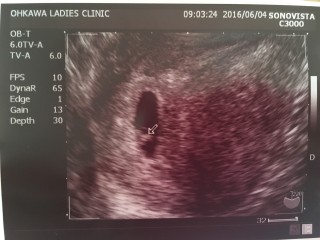

卵黄嚢、胎芽、心拍の確認が出来ました!心拍見えるかな?と先生に言われ見てみるとピコピコ動いていて安心しました。胎芽の大きさは3.3mmでした。

初投稿! 心拍確認されました♡ぴこびこ動いててすでにかわいい♡ が、なんと子宮頸がんの疑いが。。(;_;)こわいなぁ。。なにもないといいな~

今朝少量の茶オリがでたため、受診しました。 四日前は胎嚢しかみえなかったのにこの四日間で心拍確認できました! 茶オリも心配いらないようです。 安心しました!!